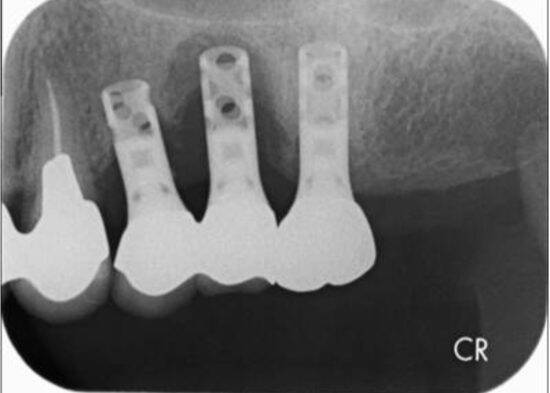

何年か前に入れたインプラントが揺れていると来院された患者さんがいました。レントゲン写真を撮ると、インプラントの周りが溶けて黒く写っています。

インプラント周囲炎とは、インプラントを支える歯茎や骨などの周囲の組織が炎症を起こす病気で、ひどくなるとせっかく埋入したインプラントが抜け落ちることもあります。その主な原因は、プラーク(歯垢)や歯石の蓄積、不十分なブラッシングなど、通常の天然歯の歯周病と変わりがありません。

残念ながら、このケースもインプラントを抜くという選択になりました。